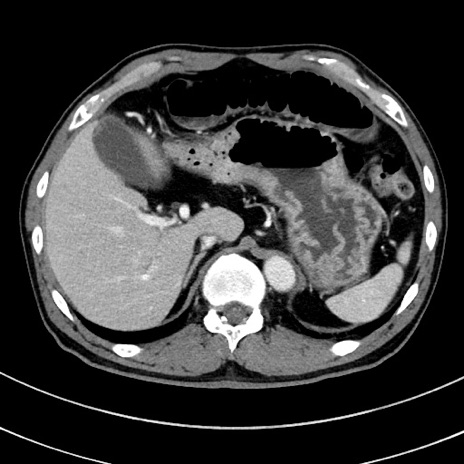

症例8(横断像)

【症例】 60歳代男性

【主訴】 黒色吐物

【現病歴】 4日前から嘔気自覚、2日前の朝食後にも嘔気あり、自分で手で嘔吐反射起こし嘔吐したところ血が混ざっていたため受診。

【既往歴】 5年前汎発性腹膜炎を伴う急性虫垂炎で手術、高血圧、前立腺肥大症、高脂血症

【身体所見】 腹部正中に手術癩痕あり 腹部平坦・軟圧痛なし膨満感あり

【データ】WBC 8400、CRP 4.54